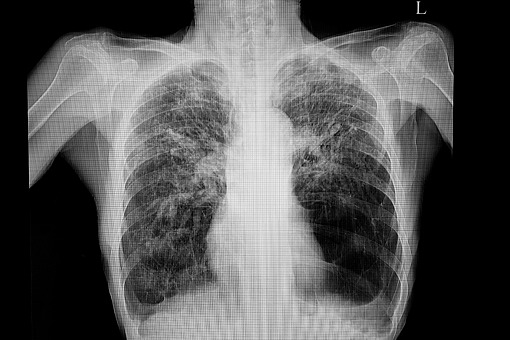

W 2022 r. ukazały się wytyczne badawcze grupy ekspertów przygotowane na podstawie przeglądu systematycznego opublikowanych prac na temat zespołu włóknienia płuc i rozedmy. Celami, które sobie postawili autorzy tej publikacji, było opisanie terminologii definicji, etiologii, charakterystycznych cech, patofizjologii, ocena współchorobowości i przebiegu włóknienia współistniejącego z rozedmą. Autorzy pracy zwracają też uwagę na konieczność zbadania, czy jest to zespół chorób, czy może dwie oddzielne niezależne od siebie choroby i określenie postępowania oraz priorytetów badawczych na przyszłe lata.

Dr n. med.Małgorzata Sobiecka, pulmonolog z I Kliniki Chorób Płuc IGiChP w Warszawie, zwraca uwagę, ze w badaniach czynnościowych stosunkowo dobrze zachowane są parametry wentylacyjne FVC, FEV1 przy nieproporcjonalnie do tego obniżonej zdolność dyfuzji dwutlenku węgla i współczynnika przenoszenia tlenku węgla. Zazwyczaj też występuję ciężka desaturacja.

Ekspertka omówiła także sposoby leczenia w świetle najnowszych badach, z uwzględniem przypadków nagłego zaostrzenia z rozedmą (typu POChP) oraz nagłego zaostrzenia związanego z włóknieniem (typu IPF), a także przyjrzała się nowej definicji włóknienie płuc z rozedmą.